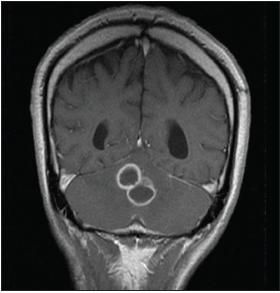

ACT scan of the head revealed a cerebellar vermian mass of 1.8 cm with associated vasogenic edema and moderate cerebral atrophy (Figure 1). An MRI scan of the brain revealed 2 predominant ring-enhancing lesions with surrounding vasogenic edema (Figure 2).

Figure 2

This MRI scan ofthe head, taken on admission,shows 2 predominant ringenhancinglesions withsurrounding vasogenicedema.